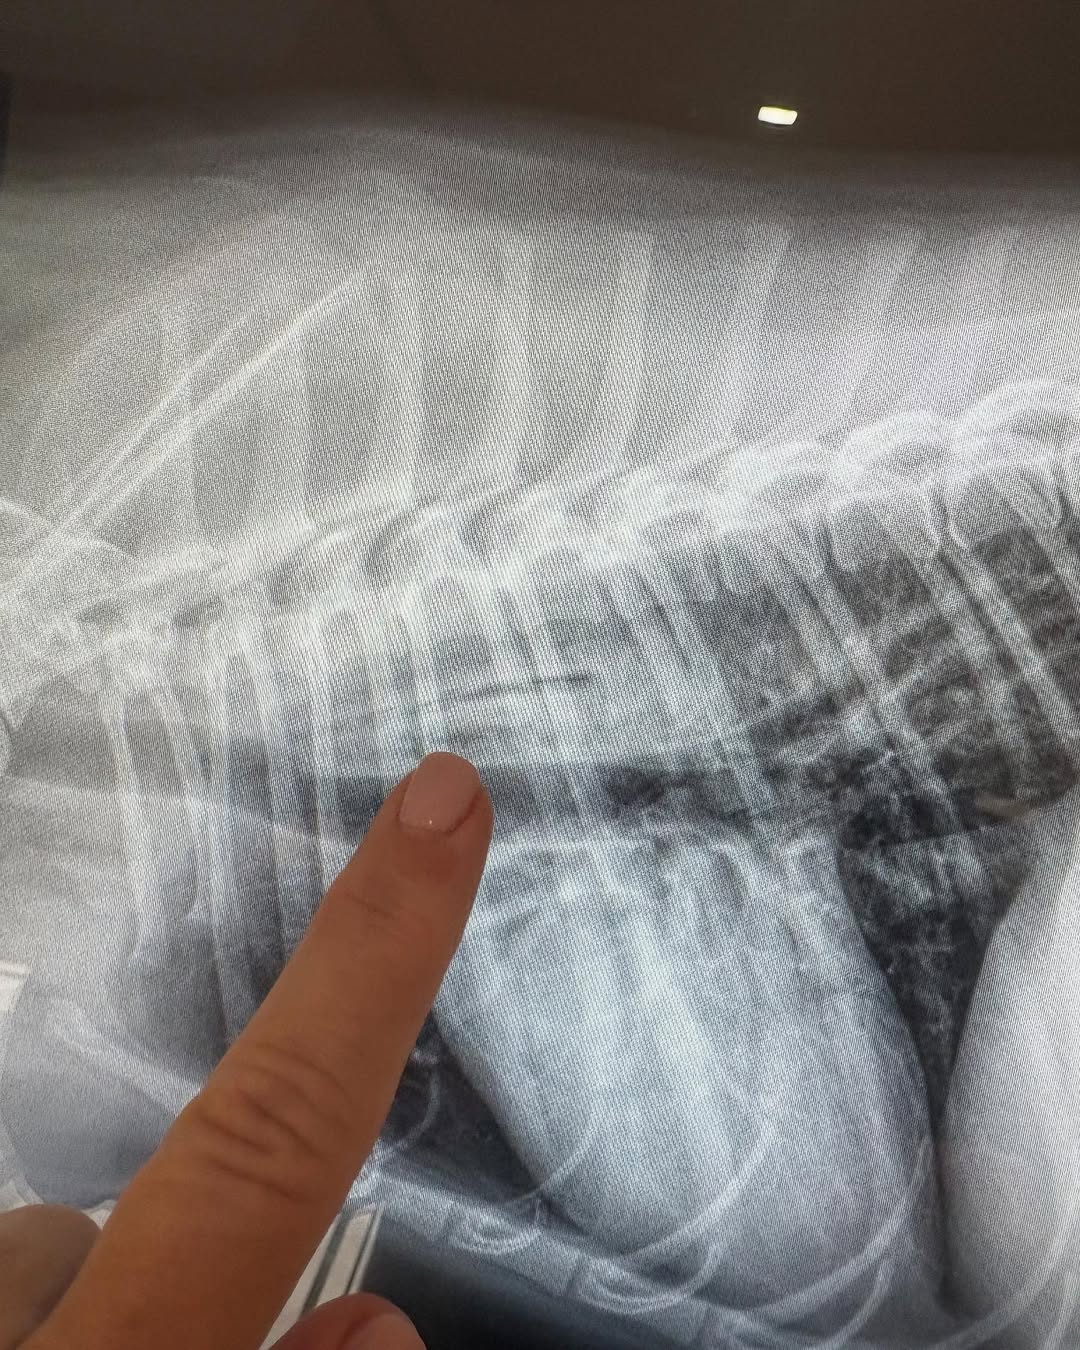

Exploratory surgery did not reveal any obstruction, so the vet ordered a barium test and brought in a specialist to examine the X-rays. That’s when the unexpected discovery was made.

Luna had swallowed a mango seed, which was lodged sideways in her throat, making it nearly impossible to detect initially.

“The puzzle pieces finally came together for LUNA as she hangs on to life. Literally. Was suspected she swallowed mango seed. Case presented as foreign body. The plot twist is the foreign body is splintered and lodged in her throat,” Jaime wrote in another post.